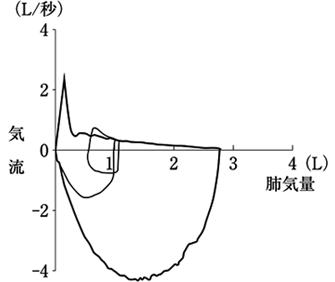

62歳の男性。スパイログラムのフローボリューム曲線を図に示す。最も考えられるのはどれか。